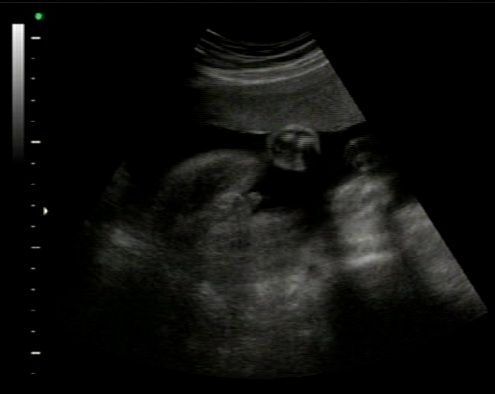

Hi all. thanks for your help! been told its a boy at 27weeks. I am interested in what you have to say.

All boy! Congrats :)

Yep, it's a boy!

Boy!

What a cute little winky, boy :)